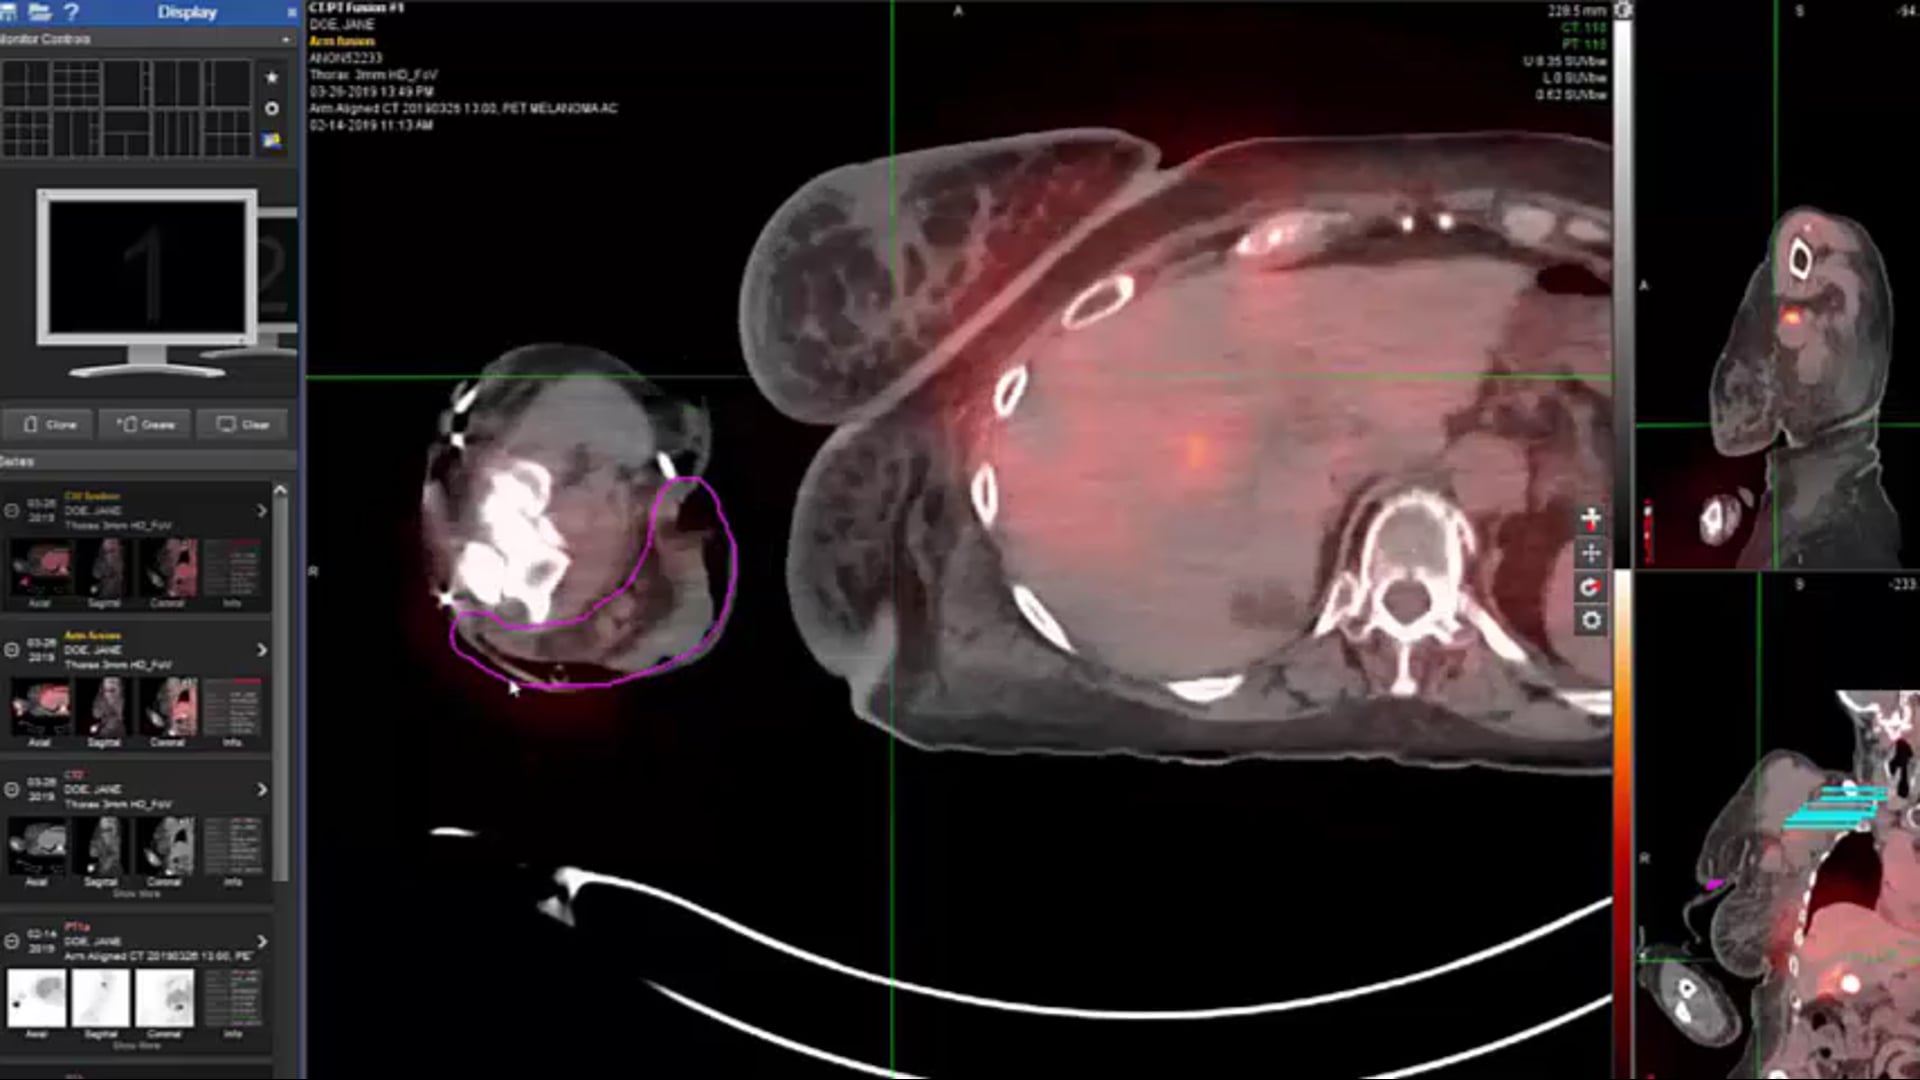

stomach METs, melanoma, palliatve care, metastatic, bleeding stomach, immunotherapy, radiation therapy, lymphoma, low grade, locally recurrent, first principles, lung tumors, steroids, prednizone, dexamethasone, oral morphine, morphine drip, vaginal discharge, MRI, primary tumors, lymph nodes, me...